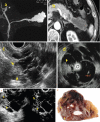

Endoscopic ultrasound (EUS) is a key modality for the evaluation of suspected pancreatic cystic neoplasms (PCNs), as the entire pancreatic gland can be demonstrated with high spatial resolution from the stomach and duodenum. Detailed information can be acquired about the internal contents of the cyst(s) [septum, capsule, mural nodules (MNs)], its relation with the main pancreatic duct (MPD), and any parenchymal changes in the underlying gland. PCNs comprise true cysts and pseudocysts. True cysts can be neoplastic or nonneoplastic. Here, we describe serous cystic neoplasm (SCN), mucinous cystic neoplasm (MCN), and intraductal papillary mucinous neoplasm (IPMN) as prototype neoplastic cysts, along with nonneoplastic lymphoepithelial cysts (LECs).